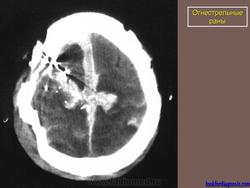

Огнестрельные раны.

Огнестрел и военные действия.

1.pulya_.29.i.slayd28.jpg2yupulya.30.i.slayd29.jpg3.pulya_.32.i.slayd31.jpg4.pulya_.33.i.slayd32.jpg